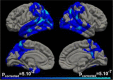

Results: Compared with asymptomatic participants, those with symptomatic Alzheimer's disease showed a pattern of cortical atrophy in posterior parieto-temporo-occipital cortices. In symptomatic subjects, trial 1 immediate free recall significantly correlated with cortical atrophy in lateral prefrontal regions. Trial 3 free immediate recall and total free immediate recall were associated with the most widespread cortical atrophy. Total immediate score was related to posterior cortical atrophy, including lateral parietal and temporal cortex, posterior cingulate cortex, precuneus, and medial temporal lobe areas. Delayed memory scores were associated with cortical atrophy in temporoparietal and medial temporal lobe regions. No significant relationships were observed between episodic memory measures and cortical atrophy in asymptomatic subjects.